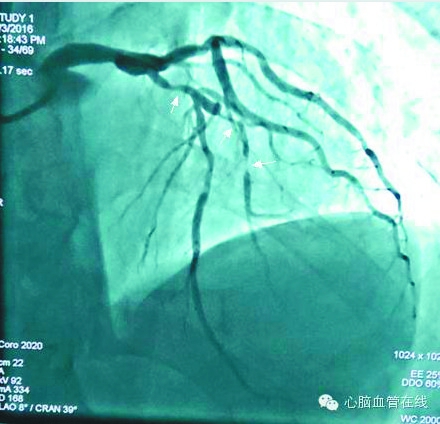

术后造影